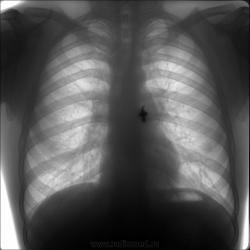

Молодой человек. В течение недели повышение t по вечерам, слабость, потливость. Вопрос не новый: отпустить или помучать?

Слева в 1 межреберье-кольцевидная тень(?).Снимок нечеткий, похоже,ЦФГ, у меня часто бывает что-то не совсем понятное на цифровых снимках, надо сделать прицельно верхние доли.

Я вбил себе в голову, что контур средостения на уровне дуги легочной артерии ненормальный. Глюки?

На мой взгляд, не "глюки", а реальность.

Да, и еще есть, за что глаз цепляется.

Архив есть, но я его не сбросил на флэшку. При ретроспективном просмотре на работе картина стабильная за последний год (на мой взгляд). Еще смущает затенение передне-верхнего средостения.

Ну, в "местах не столь отдаленных", надо думать, что прогрессирование процесса пойдет, и для динамики "года" ждать не придется. Но вот есть опасение, именно с учетом того места, которое Вы пометили стрелочками (да, мне и "тело" правого корня, как-то не симпатично), что тут может вылезни не "специфика".

Вообще-то, первая мысль была об объеме в средостении (тимома?). В понедельник буду резать, с комментариями коллег - более уверенно.

Во-первых, слегка расширенный контур (стрелки). Во-вторых, затененное средостение (овал). В-третьих, тимома - это очень предположительно, может оказаться и что-то другое, хотя бы и норма.

согласна с Валентином Львовичем, на мой взгляд, корни расширены, и в s6 как-то прозрачность снижена

Дефигурация  тени средостения слева есть, но это может быть за счёт поворота. Проще всего развеять сомнения на R-скопии лёгких.